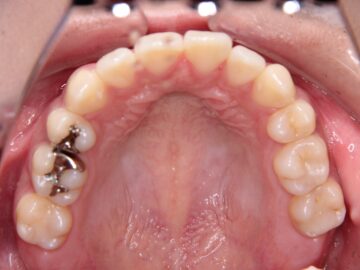

ご相談時

歯ぐきが薄く口唇がわずかに突出しているため、小臼歯抜歯での治療を勧めた。

| 抜歯部位 | 上顎左右測第一小臼歯、下顎左右測第一小臼歯 |